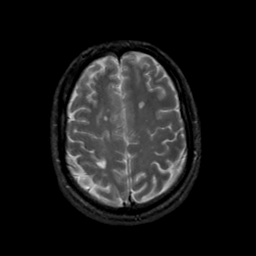

MR Study #19, August 25, 1991 -- Slice #38

[Home][Help][Clinical][Tour 1][Tour 2] Slice 38